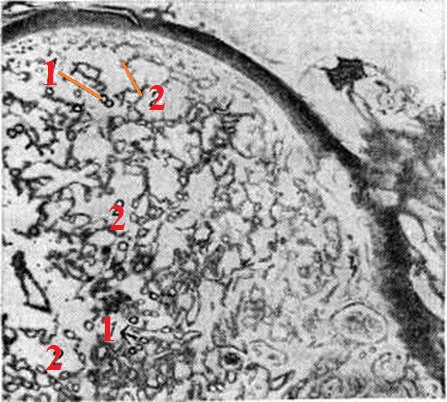

Патогистология: разрастания грануляционной ткани с большим количеством расширенных с набухшим эндотелием капилляров (рисунок 1), строма отёчна, иногда содержит воспалительный инфильтрат, состоящий из лимфоцитов, тучных клеток, в более поздних стадиях — из фибробластов.